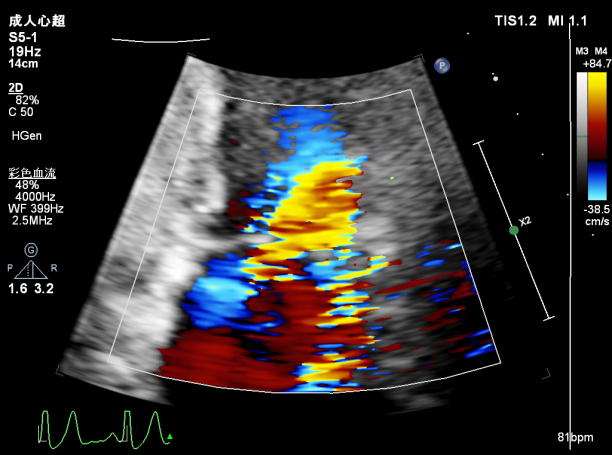

肺静脉血流频谱逐渐恢复正向

肺静脉血流频谱恢复正向

肺静脉血流频谱完全正向